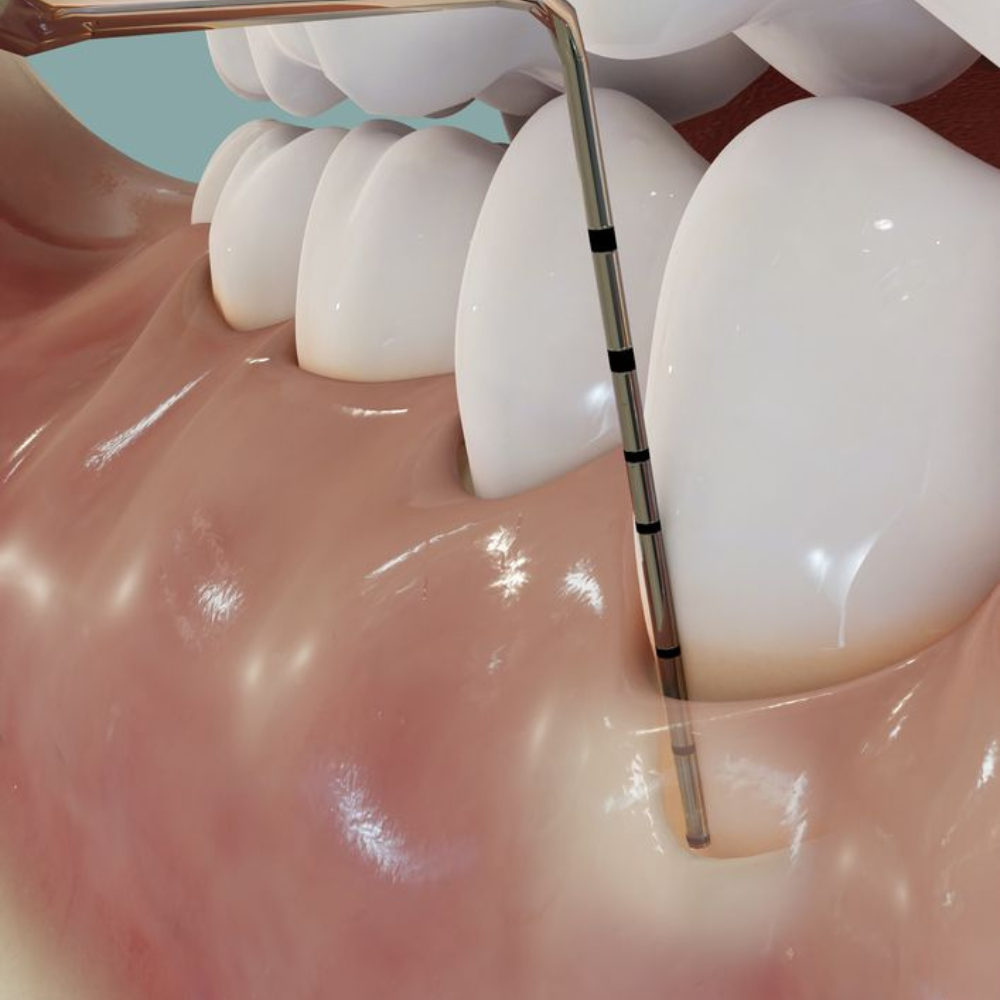

- Diagnóstico (sondaje, radiografías)